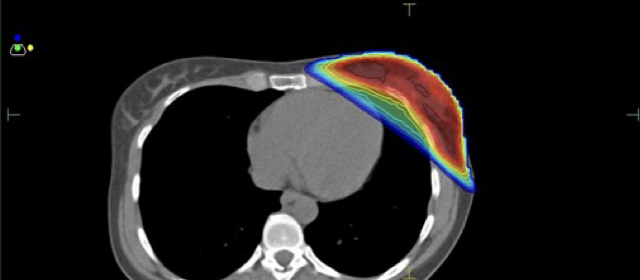

Πραγματοποιείται ακτινοβόληση σε καθορισμένη φάση της αναπνοής κατά την οποία αυξάνεται η απόσταση της καρδιάς από τον μαζικό αδένα μειώνοντας και τον όγκο του πνεύμονα ο οποίος ακτινοβολείται.

Κατανομή δόσης με την τεχνική ABC

Ελαχιστοποίηση δόσης στην καρδιά και τον πνεύμονα